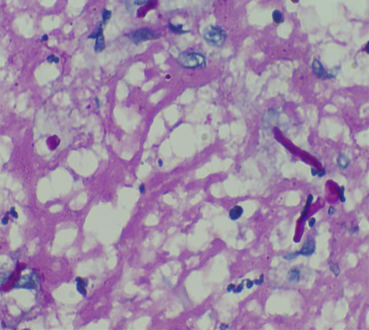

Upon microscopic examination, sections showed a well-circumscribed necrotizing lesion with palisading granulomas containing giant cells (Figure 3 [Fig. 3]). There were also areas of an old hemorrhage and cholesterol cleft formation. Staining for acid-fast bacteria was negative. The periodic-acid Schiff with diastase (PAS-D) stain (Figure 4 [Fig. 4]) and Grocott’s methenamine silver (GMS) stain both showed branching, septate fungal hyphae (Figures 5 [Fig. 5]). The diagnosis of a fungal abscess consistent with subcutaneous phaeohypomycosis was made, since the lesion was well circumscribed. No immediate antifungals started. Anti-diabetic measures were implemented and followed very strictly. The patient showed no recurrence or dissemination during 10 months of follow-up.

Figure 4: PAS-D staining (400x) showing branching, septate fungal hyphae